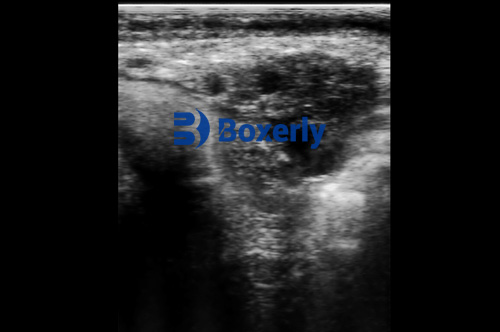

Cows may appear healthy but still carry infections that affect fertility. Traditional methods like palpation or observation often fail to detect these subclinical cases. Ultrasound provides a clear picture of the uterine lining, fluid accumulation, and tissue abnormalities, enabling early intervention before problems worsen.

Ultrasound allows veterinarians and farmers to see changes in the uterus that indicate infection. Fluid buildup, thickened endometrial walls, and irregular tissue textures can all be detected non-invasively.